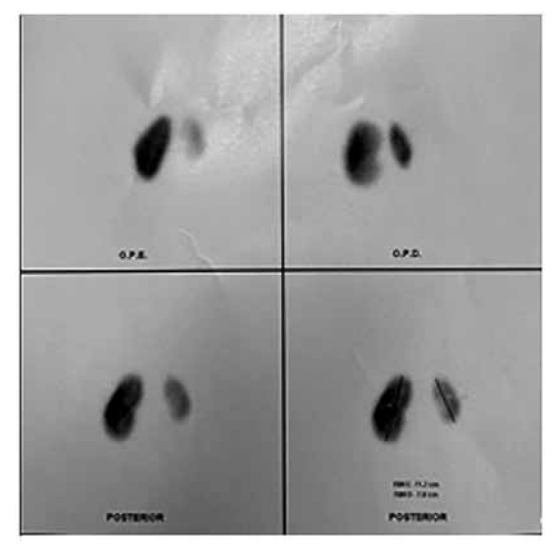

Criança de 2 anos, sexo feminino, apresenta infecção

do trato urinário de repetição. No exame de ultrassom,

apresentava dilatação bilateral de pelve renal e ureteral.

Realizado UCM e DMSA com seus resultados apresentados a seguir:

Refluxo vesicoureteral, Up to DaTe)

(Arquivo pessoal; imagem usada com autorização)

Considerando o contexto e as imagens, assinale a alternativa que indica o grau de refluxo demonstrado na UCM e a correta avaliação pelo DMSA.